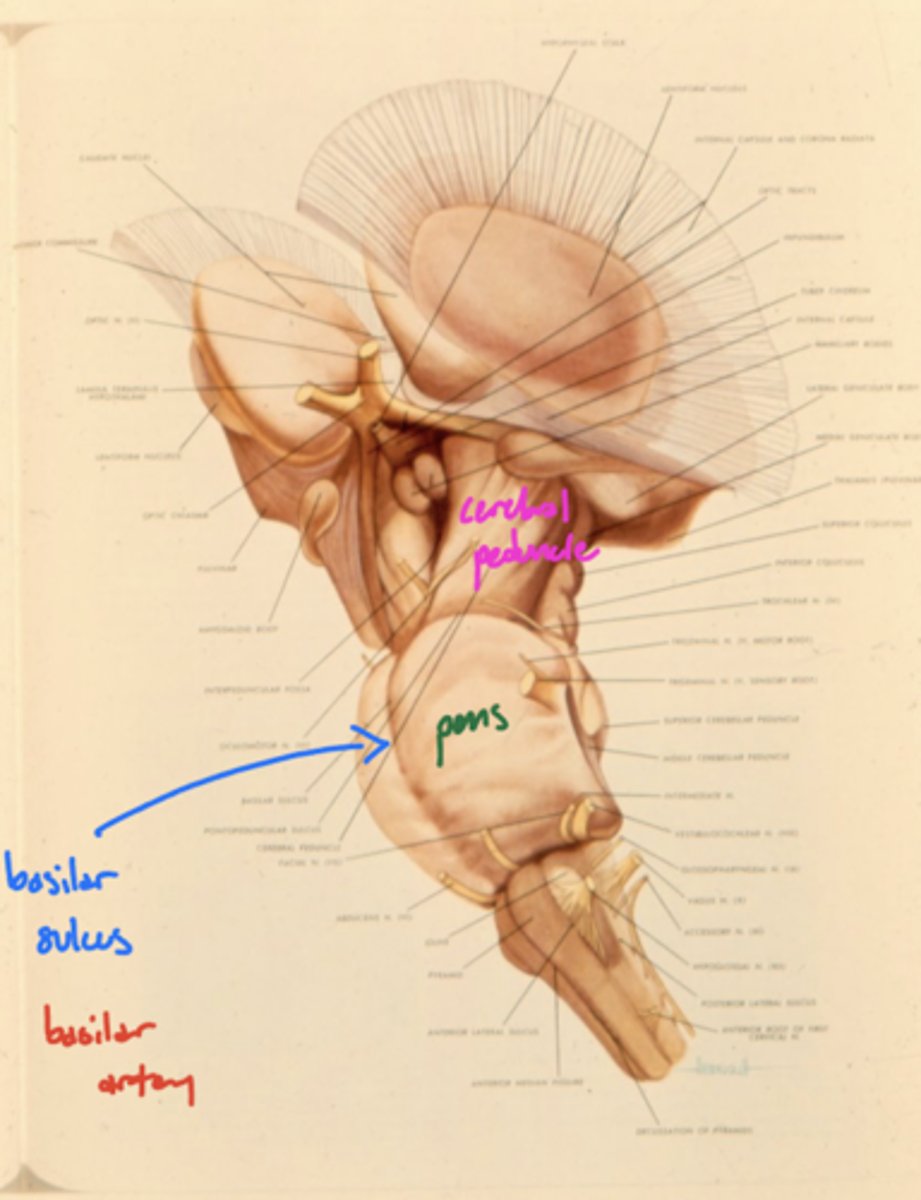

Where is the basilar sulcus?

ventral pons

What runs in the basilar sulcus?

basilar artery

What is the floor of the 4th ventricle?

tegmentum pons

image -- green

What cranial nerve nuclei are in the tegmentum pons?

1. CN V (5)

2. CN VI (6)

3. CN VII (7)

4. CN VIII (8)